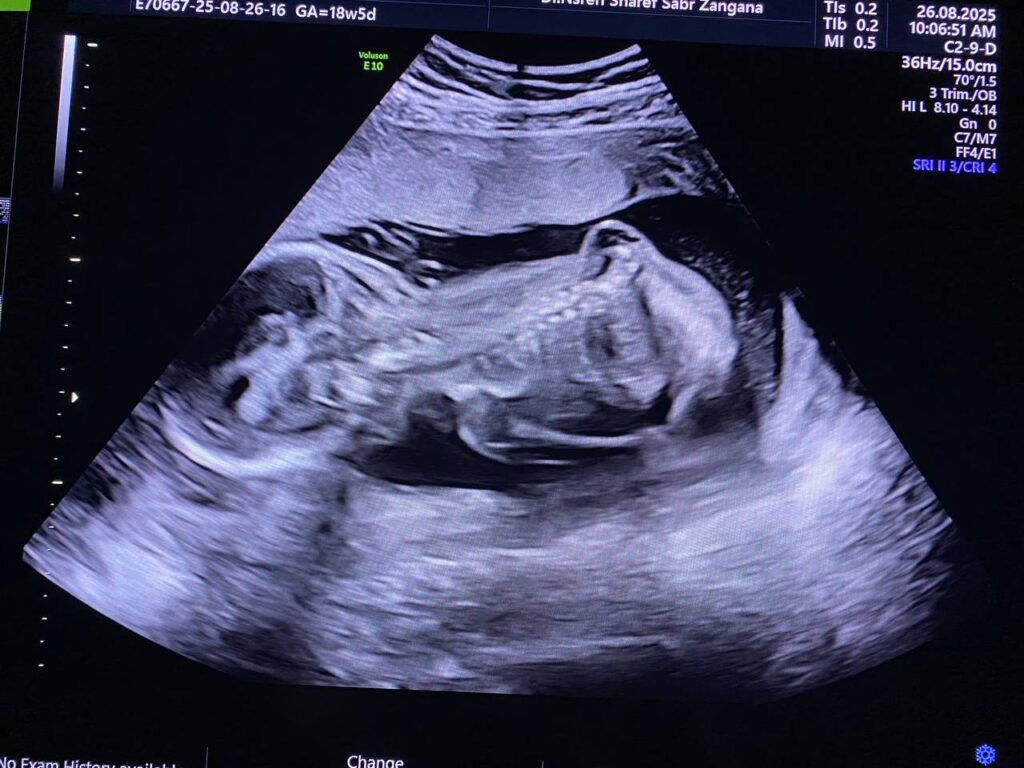

Multiple congenital anomaly seen , brain show hydrocephaly , lumbosacral myelomeningocele 18x19mm , both hips and femurs are abducted with flexed both legs , and both feet show rocking feet morphology , both hands are also fisted , mostly Arnold Chiari Malformation type 2 ?? or other congenital anomaly , for further study ( genetic study )

Normal in amount of liquor

F.L. = 18w+5d

B.P.D. = 19w+1d

Fetal body weight about =306gram, A.C = 40%